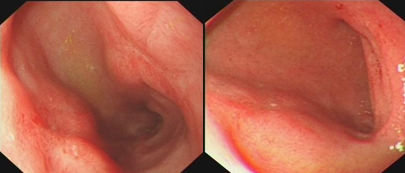

反流性食管炎

(1994年 洛杉矶诊断标准)

内镜下见食管下端粘膜破损(糜烂、溃疡),共分4级。

单纯的食管粘膜水肿或充血不诊断为RE。

A级:粘膜破损局限于粘膜皱襞上,且长度<0.5cm;

B级:粘膜破损局限于粘膜皱襞上,其中至少一个粘膜破损长度>0.5cm;

C级:粘膜破损相互融合,但少于食管周径的75%;

D级:粘膜破损相互融合,至少侵犯食管周径的75%以上。存在Barrett食管或食管狭窄均分入D级。